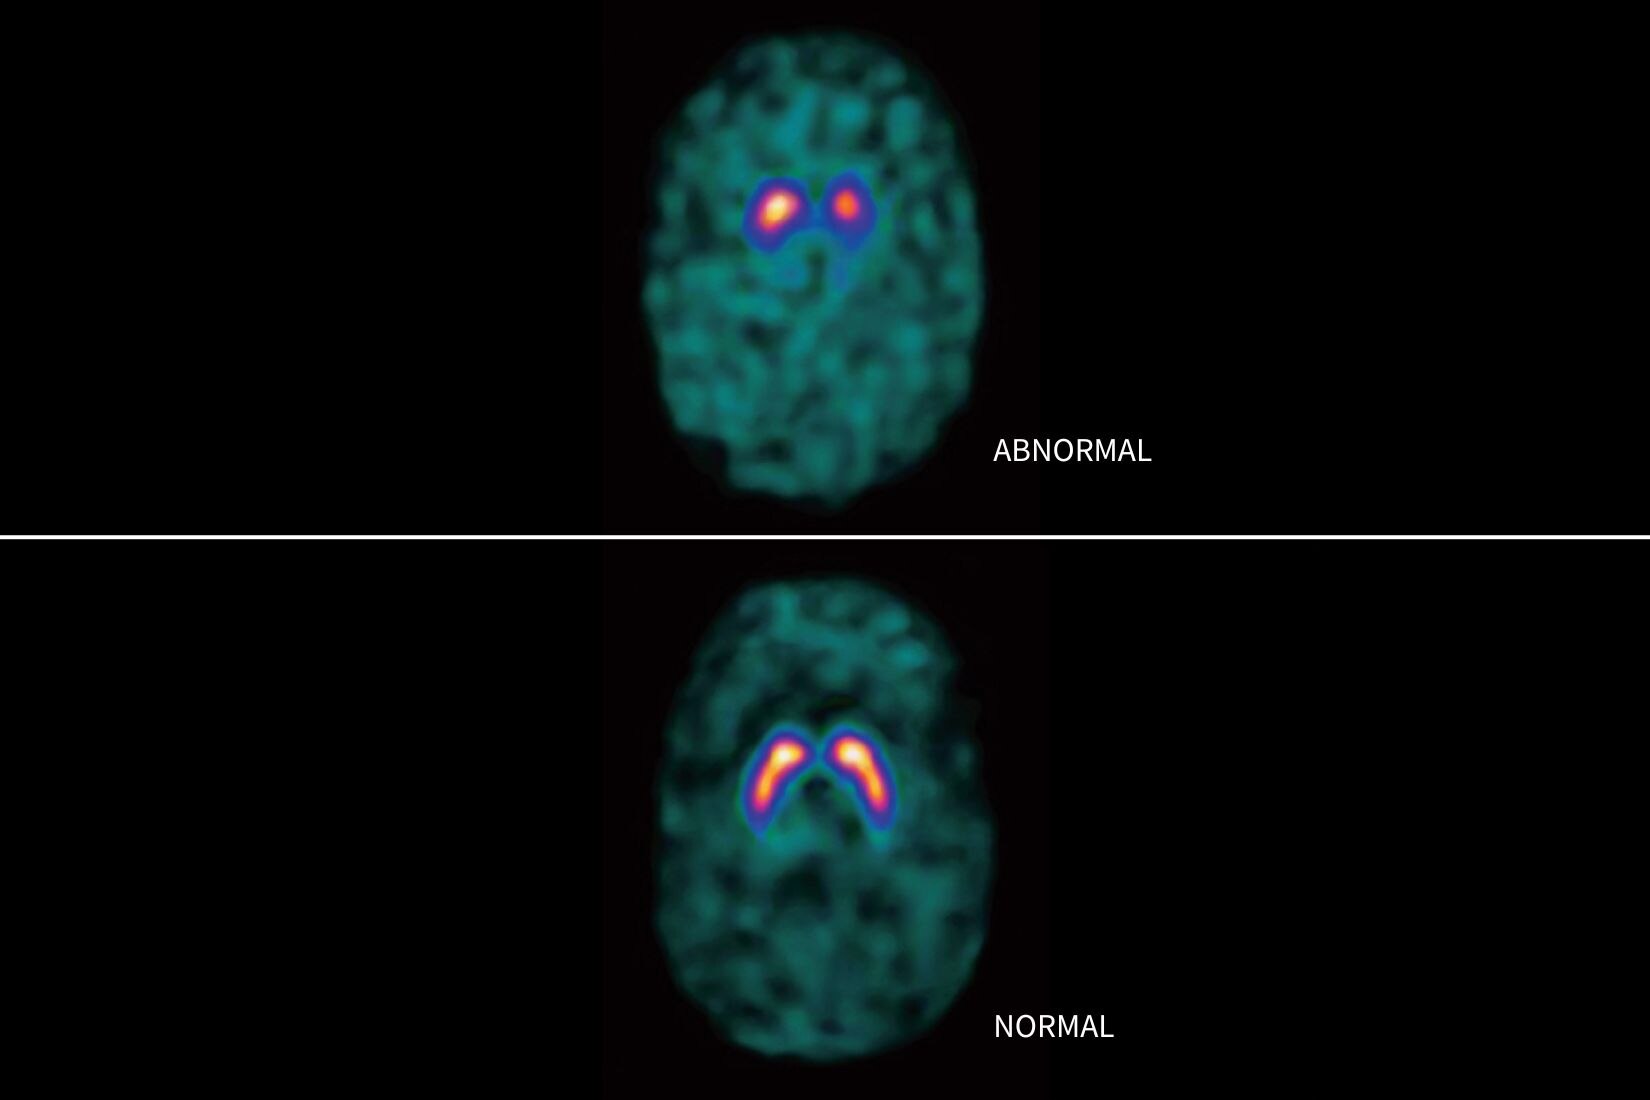

SIGNA™ Champion offre un design modulare con opzioni software e hardware pronte per soddisfare le priorità cliniche. Include strumenti di base e avanzati e soluzioni per la qualità delle immagini come AIR™ Recon DL e Sonic DL™. Queste applicazioni consentono non solo di ottimizzare i casi di routine, ma anche di operare in altri campi specifici come neurologia, apparato muscolo-scheletrico, cardiologia e oncologia. E non è tutto. SIGNA™ Champion è in grado di offrire configurazioni a 32, 48 e 64 canali per garantire la massima flessibilità e semplificare la configurazione delle bobine sulla base delle diverse anatomie.

AIR™ Recon DL

AIR™ Recon DL potenzia le funzionalità della tua RM offrendo una qualità dell'immagine superiore con tempi di scansione ridotti.